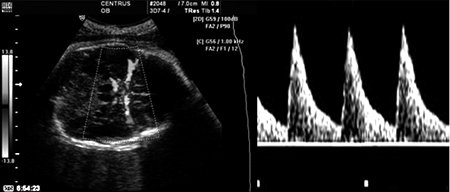

Καταρχήν, το πρώτο αγγείο που εξετάζεται είναι η μητριαία αρτηρία της μητέρας,

όπου κατά τη διάρκεια της κύησης, η αντίσταση ροής ελαττώνεται. Η αρχική πτώση

γίνεται μεταξύ των 24-26 εβδομάδων της κύησης και οφείλεται στην τροφοβλαστική

διείσδυση των σπειροειδών αρτηριών, ενώ το γεγονός ότι η ελάττωση αυτής της

αντίστασης συνεχίζεται, πιθανόν να εξηγείται από ορμονικούς παράγοντες που δρουν

στην ελαστικότητα των αρτηριακών τοιχωμάτων. Η χαρακτηριστική φυσιολογική κυματομορφή

των μητριαίων έχει υψηλή διαστολική ροή, ενώ απουσιάζουν οι εγκοπές στην αρχή

της (εικόνα 4). Για να ληφθεί η κυματομορφή της μητριαίας αρτηρίας τοποθετείται

ο ηχοβολέας στην παραμήτρια περιοχή και περιστρέφεται η κεφαλή, ώστε να βρεθεί

η μητριαία αρτηρία που ξεκινά από την έξω λαγόνια αρτηρία.

Ομφαλική αρτηρία

Είναι το πρώτο εμβρυικό αγγείο που μελετήθηκε με το Doppler. Ο ομφάλιος λώρος,

για τη μεν ομφαλική αρτηρία έχει τη χαρακτηριστική οδοντωτή μορφή προς τη μια

κατεύθυνση, ενώ για την ομφαλική φλέβα, συνεχή ροή προς την άλλη (εικόνα 5).

Η λήψη προτιμάται να γίνεται από ένα ελεύθερο τμήμα του λώρου, μακριά από την

αρχή ή το τέλος του. Ο δείκτης παλμικότητας ελαττώνεται όσο προχωρούμε από την

εμβρυική πλευρά προς την πλακουντιακή. Η ροή στην ομφαλική φλέβα αυξάνεται με

την εισπνοή και ελαττώνεται με την εκπνοή, ενώ επίσης ανάλογες αλλαγές υπάρχουν

και στο δείκτη παλμικότητας της ομφαλικής αρτηρίας, οπότε καλό είναι να αποφεύγεται

η εξέταση κατά τη διάρκεια της εμβρυικής αναπνοής. Με την πρόοδο της κύησης

αυξάνεται η τελοδιαστολική ταχύτητα ενώ ελαττώνονται οι δείκτες αντίστασης.